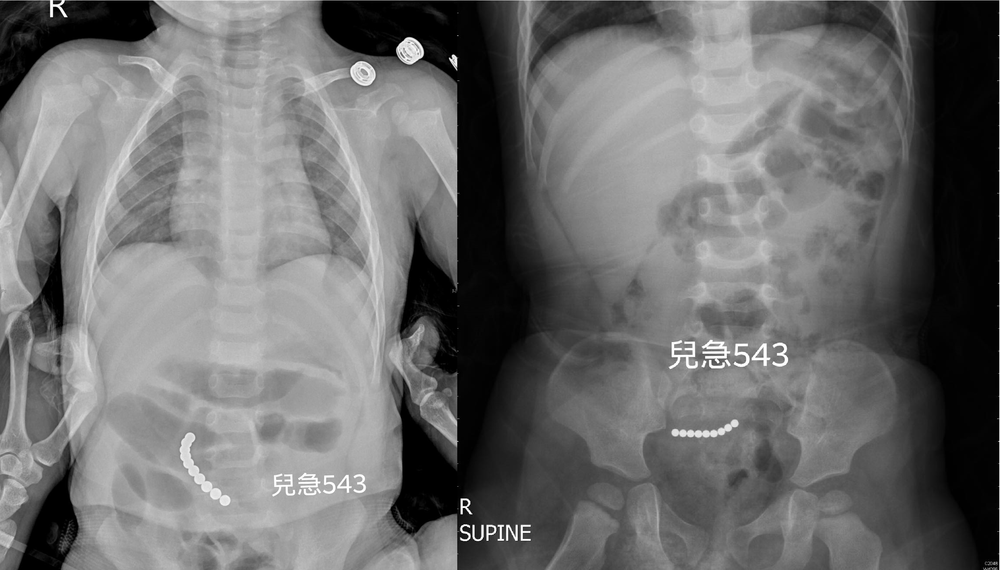

- 大二醫學生爆代刀手術 成大:僅外皮縫合2021/11/09